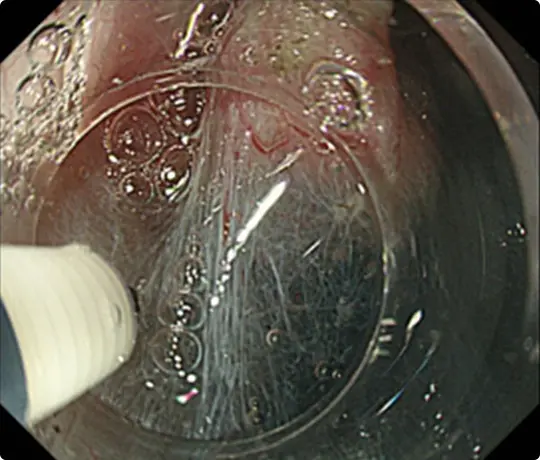

生理食塩水の中で行うESDです。水中では光の反射による視野障害がなくなり、自然な拡大効果もかかるため、鮮明な視野が得られます。

全国的にもまだ出来る病院が少ない十二指腸ESDを提示します。十二指腸ESDではUnderwater ESD(生理食塩水の中で行うESD)が有効です。

約25mmの十二指腸腫瘍を認めます。

Underwater ESD(生理食塩水の中で行うESD)を行うことで光の反射がなくなり、拡大効果もあるため、精密に剥離することが可能になります。

約4cmの高度な線維化を伴う早期大腸がんに対するESDを提示します。当科で考案したUnderwater ESD(生理食塩水の中で行うESD)が有効でした。

重症の潰瘍性大腸炎の既往があり、高度な線維化により難易度が高いと予想されました。

粘膜の下に液体を注入して病変を浮かせます。

病変の外側の粘膜を電気メスで切開したところです。

粘膜の下の組織(粘膜下層)を電気メスで剥がそうとしていますが、高度な線維化で筋層との境界がよく分かりません。このままでは筋層を傷つけて穴をあけてしまうリスクがあります。

当科で考案したUnderwater ESD(生理食塩水の中で行うESD)を行うことで光の反射がなくなり、拡大効果もあるため、鮮明な視野が得られ粘膜下層と筋層の境界が分かりやすくなります。筋層を傷つけないように、精密に剥離することが可能になります。

穿孔(壁に穴があくこと)などの問題なく、病変を切除しました。切除後は潰瘍が出来ますが、1~2ヵ月で治ります。